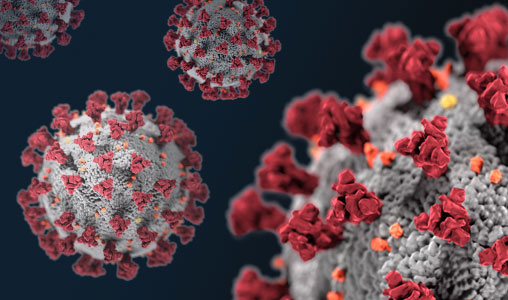

Immagine: un’immagine con ingrandimento di potenza maggiore mostra la struttura e la densità dei virioni SARS-CoV-2 (rossi) prodotti dagli epiteli delle vie aeree umane. Credito:Ehre Lab, UNC School of Medicine.

Immagine: virioni SARS-CoV-2 (rosso). Credito: Ehre Lab, UNC School of Medicine.

Le immagini, ricolorate dallo studente di medicina dell’UNC Cameron Morrison, mostrano cellule ciliate infette con filamenti di muco (gialli) attaccati alle punte delle ciglia (blu). Le ciglia sono le strutture simili ai capelli sulla superficie delle cellule epiteliali delle vie aeree che trasportano il muco (e i virus intrappolati) dal polmone. Un’immagine con ingrandimento di potenza maggiore mostra la struttura e la densità dei virioni SARS-CoV-2 (rossi) prodotti dagli epiteli delle vie aeree umane. I virioni sono la forma completa e infettiva del virus rilasciata sulle superfici respiratorie dalle cellule ospiti infette.

Questa ricerca di imaging aiuta a illustrare il numero incredibilmente alto di virioni prodotti e rilasciati per cellula all’interno del sistema respiratorio umano. Il grande carico virale è una fonte di diffusione dell’infezione a più organi di un individuo infetto e probabilmente media l’alta frequenza della trasmissione di COVID-19 ad altri. Queste immagini rappresentano un valido motivo per l’uso di maschere da parte di individui infetti e non infetti per limitare la trasmissione di SARS-CoV-2.